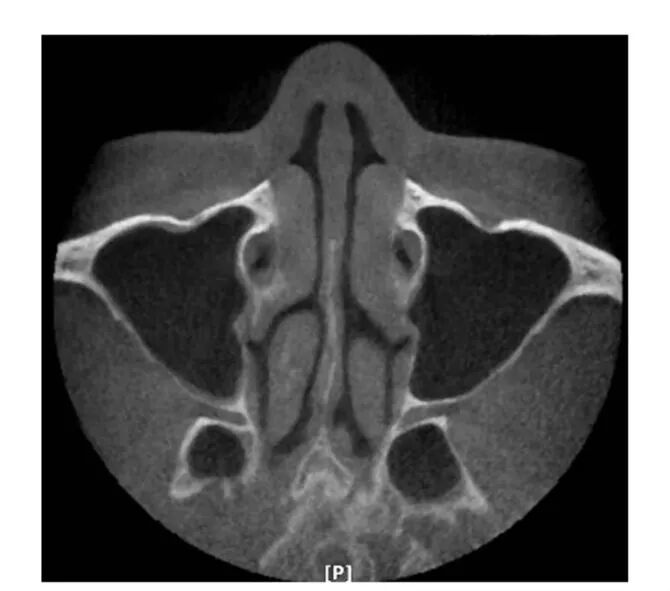

1.鼻中隔( nasal septum) ; 2.右侧中鼻甲( right middle nasal concha) ; 3.上颌窦后壁( posterior wall of maxillary sinus) ; 4.颧颞缝( zygomaticotemporal suture) ; 5.颞骨( temporal bone) ; 6.外耳道( external acoustic meatus) ; 7.上颌窦前壁( anterior wall of maxillary sinus) ; 8.左侧上颌窦( left maxillary sinus) ; 9.犁骨( vomer) ; 10.翼腭窝( pterygopalatina fossa) ; 11.翼突( pterygoid process) ; 12.下颌髁突( mandibular condyle) ; 13.乳突气房( mastoid cells)